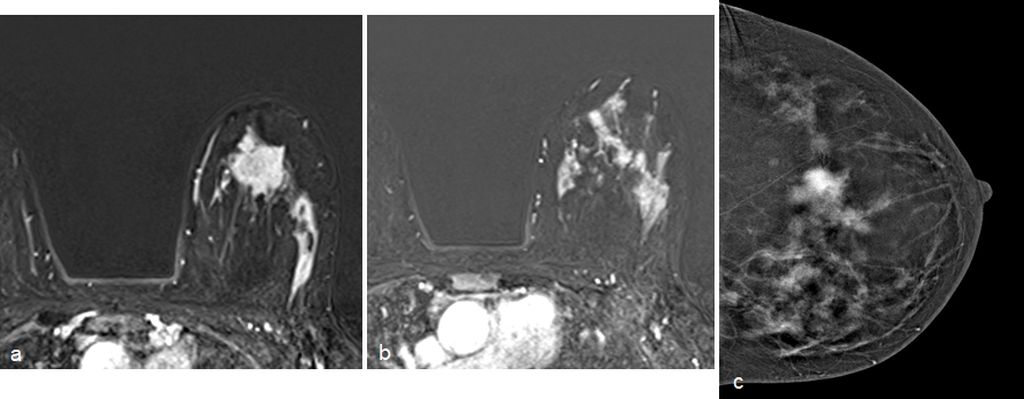

Low energy 2D mammogram images of both breasts in CC and MLO views (figure 1) demonstrate focal asymmetry with architectural distortion in the upper central quadrant of the middle third in the left breast with associated architectural distortion. Fine pleomorphic calcifications in regional distribution are noted in the inner central and upper inner quadrants of the left breast (figure 2). Diffuse skin and trabecular thickening is noted in the left breast. On post contrast recombined images (Figure 3), the area of focal asymmetry shows a heterogeneously enhancing mass with washout on delayed image (MLO). Heterogeneous and clumped non-mass enhancement in diffuse distribution is noted involving the areas of calcifications in the inner quadrant (red circle in figure 4) which could represent calcified ductal carcinoma in situ (DCIS) as well in the outer quadrant (green circle in figure 4) which could represent non-calcified DCIS. To differentiate between non-mass enhancement in diffuse distribution and background parenchymal enhancement, comparison with the opposite breast should be done. In our case there is minimal background parenchymal enhancement in the right breast (figure 3a and 3c) whereas clumped enhancement in diffuse distribution in the left breast (figure 3b and 3d) suggestive of non-mass enhancement in the left breast. Ultrasound correlation revealed an irregular isoechoic mass with indistinct margins with no posterior features measuring 2.2x1.9x1.6cm at 11:30 O'clock position, 6cm fn in left breast. It is hard on elastography (Figure 5). Non-mass ductal abnormalities in the form of irregular prominent and dilated ducts filled with soft tissue and echogenic foci within are noted in upper inner, lower inner and upper outer quadrants of left breast (Figure 6). The whole abnormality extends from the 8-12-3 o'clock position of the left breast. On tomo slices two equal density lesions with indistinct margins are noted in the upper outer quadrant of the right breast. On post contrast recombined images, they show heterogeneous enhancement. Ultrasound correlation revealed two hypoechoic lesions with circumscribed margins in the upper outer quadrant. Multiple enlarged left level I and level II lymph nodes are noted, which show asymmetrical cortical thickening and loss of fatty hilum (figure 7). MRI post contrast subtraction axial images (figure 8a and b) revealed a lesion with irregular shape and margins in the upper central quadrant of left breast with associated non-mass enhancement in diffuse distribution in upper inner, upper outer and lower inner quadrants confirming the mammographic extent of abnormalities (figure 8c).